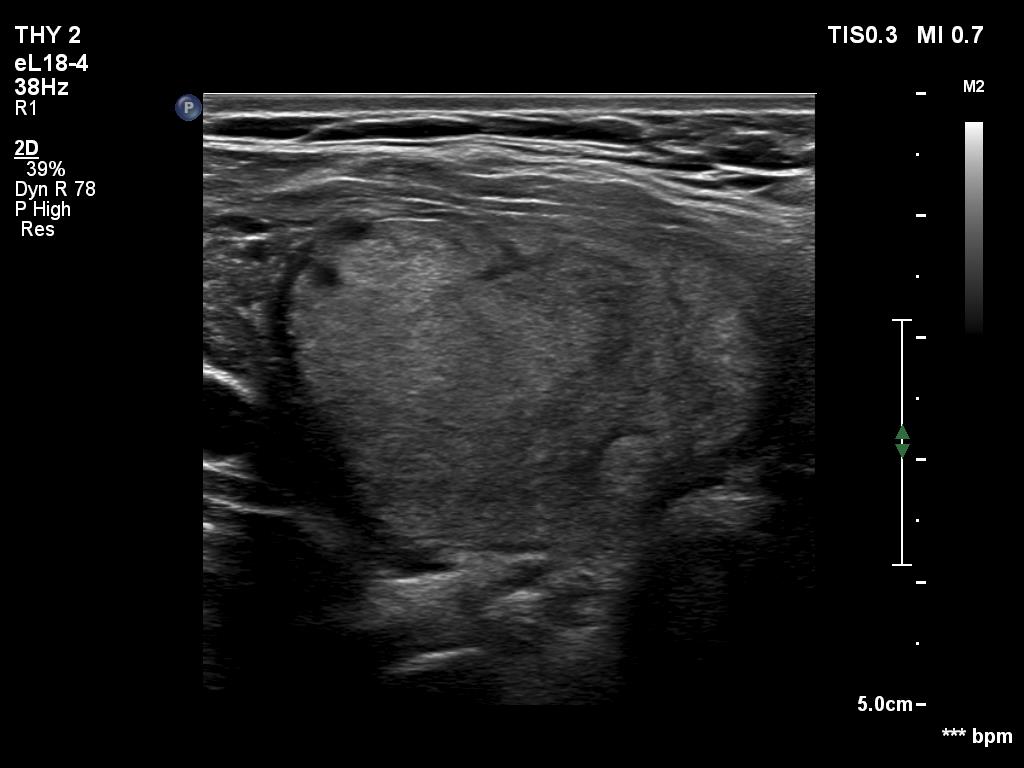

Benign nodule in Hashimoto's thyroiditis (cytology) - case 1286

Transverse scan

The iso/hyperechoic nodule has irregular margins. However, these are caused not by the infiltrative growth of the nodule but the infiltrative nature of the underlying autoimmune thyroiditis. Therefore, this nodule is an EU-TIRADS 3 lesion.